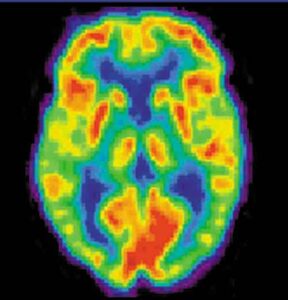

Sono stati identificati i test che prevedono meglio se una persona con problemi cognitivi potrebbe sviluppare l'Alzheimer: sono la tomografia...